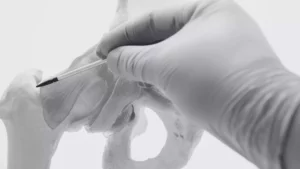

Cirurgia de Quadril

Fratura do Quadril

Navegando pela Recuperação de uma Fratura do Quadril O que é uma Fratura do Quadril? Uma Fratura do Quadril geralmente envolve uma das três áreas

dr eduardo araujo especialista em fraturas pelve acetabulo